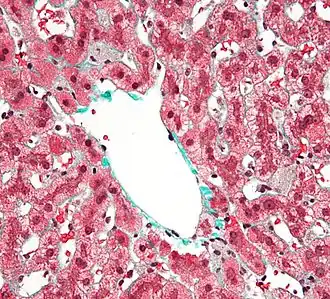

![]() Biopsia hepática en la que se observan células de Kupffer centrolobulares, con un citoplasma granular de color gris, en una lesión hepática teñida con tricrómico de Masson. | ||

Las células de Kupffer, también conocidas como células de Browicz-Kupffer, son macrófagos localizados en el hígado formando las paredes de los sinusoides que forman parte del sistema reticuloendotelial (SRE).